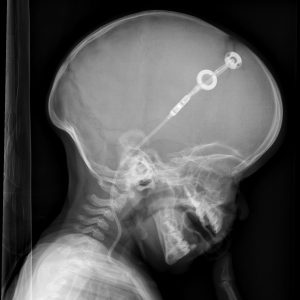

Häufig entwickelt sich beim Ungeborenen ein Hydrocephalus (sog. Wasserkopf, kurz HC). Dieser entsteht, da das Gehirnwasser (Liquor) durch die Spina bifida (und ggf. durch die dadurch bedingte Arnold Chiari Malformation) nicht mehr ideal über das Rückenmark zirkulieren kann. Durch diese Störung des Kreislaufs sammelt es sich so in den Hirnkammern (Ventrikeln) an. Dieser Hydrocephalus, der optisch nicht sichtbar oder sichtbar sein kann, wird durch die Anlage eines Ableitungs-Systems (Shunt) nach der Geburt behandelt und verursacht dann in der Regel keine Probleme mehr. Die Anlage eines Shunts wird als Routine-Eingriff bezeichnet und die Kinder sind danach sehr schnell wieder fit. Eine kognitive Einschränkung ist bei Spina bifida höchst selten, aber möglich.

©privat

Wir empfehlen hier bitte keine Google-Bildersuche zum Thema Hydrocephalus zu starten. Diese Bilder zeigen oft einen unbehandelten HC, wie er heute dank moderner Behandlungsmethoden nicht mehr vorkommt. Manchmal zeigt sich der HC über vergrößerten Kopfumfang oder Vorwölbungen der Stirn, was sich aber mit Anlage des Shunts zurückbildet.